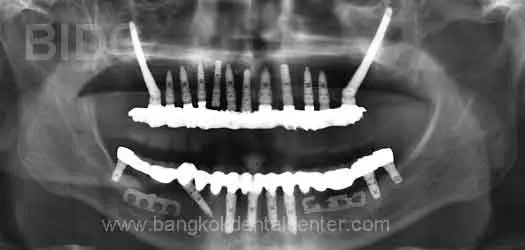

ตัวอย่างภาพของผู้ป่วยที่เข้ารับการปลูกรากเทียมด้วยระบบ Zygoma ที่ศูนย์ทันตกรรม BIDC

รากเทียมระบบ Zygomatic พร้อมสะพานฟันบนขากรรไกรบนและรากเทียมพร้อมสะพานฟันบนขากรรไกรล่าง

คำวินิจฉัย : สภาพฟันมีโอกาสและทางเลือกในการรักษาน้อย

วิธีการรักษา : รากเทียมระบบ Zygoma พร้อมสะพานฟันเพื่อทดแทนฟันบนขากรรไกรบน และรากเทียมพร้อมสะพานฟันบนขากรรไกรล่าง

ผู้ป่วยเดินทางมาจาก : ยุโรป